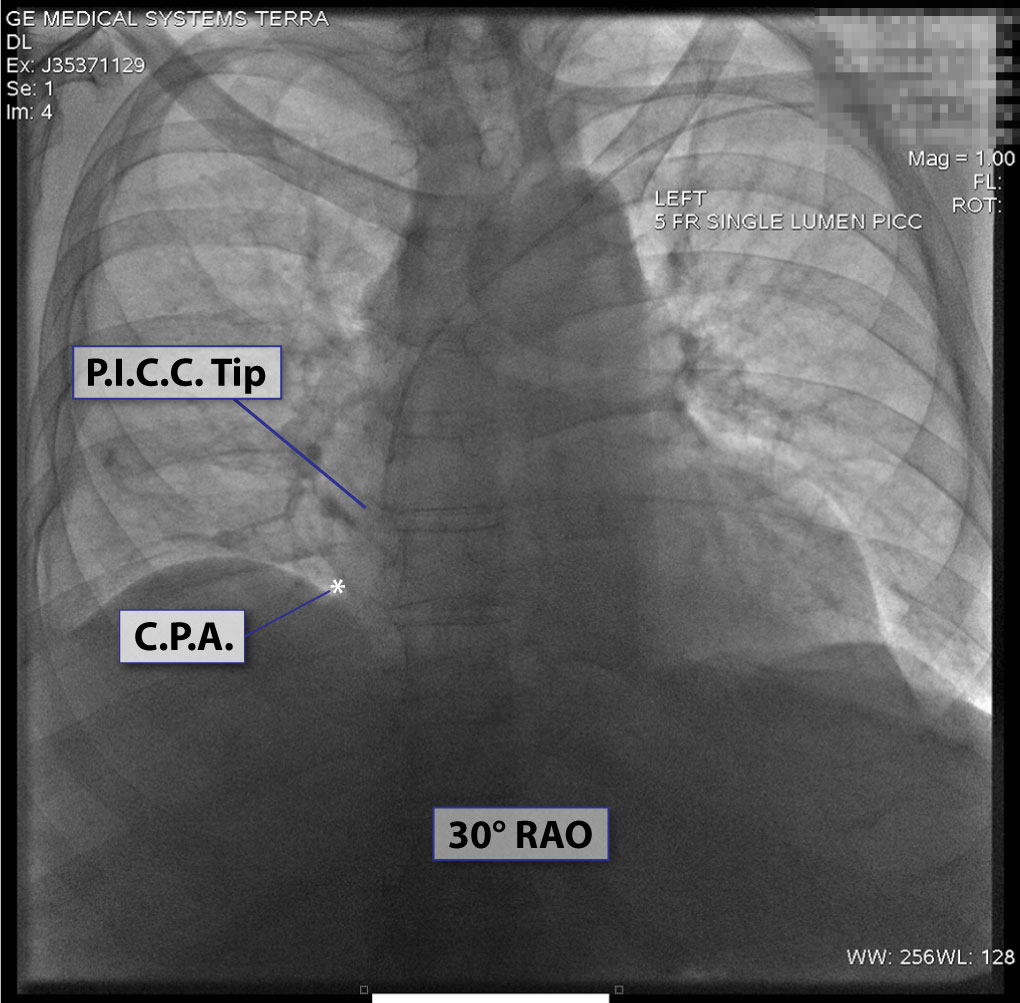

3. Chest x-ray rotation tissues: Not infrequently, the chest x-ray will be rotated causing the right cardiac margin to deviate from its normal AP appearance. In such situations, depending on the degree of rotation, an estimation of the SWEET SPOT™ is all that may be possible. In such circumstances, the right cardiophrenic angle is the most reliable anatomic landmark. Since the right atrium is immediately cephalad to a normally positioned right cardiophrenic angle, a reliable estimation of acceptable catheter tip location is still possible. The height, and consequently the width of the rectangular Sweet Spot™ box will be less exact and therefore a relatively short catheter tip position may require a non- rotated chest x-ray to confirm an acceptable location. Aim for the right atrium. See Figs. T.1, T.2, and T.3.

7. A left-sided approach often causes the tip of the venous access device to curve to the patient's left, necessitating a relatively wide SWEET SPOT™ design. See Fig.# 10 - Gallery.

8. Even on normal frontal chest x-rays, there can be significant variation in the appearance of the cardiomediastinal silhouette which can result in slight subjectivity in the exact location of the margins of the SWEET SPOT™. The closer the catheter tip is to the cavoatrial junction, the less this matters.